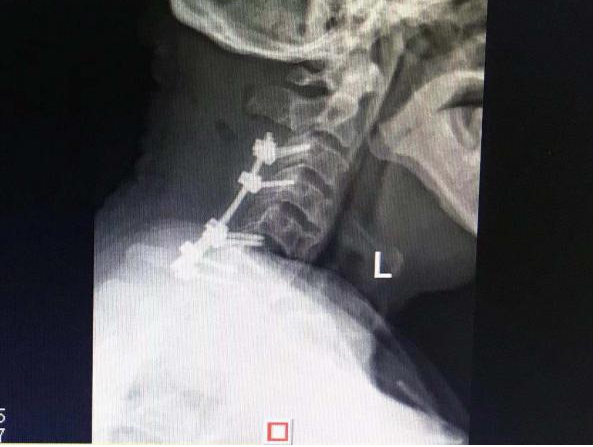

术前

术后

在有效控制基础疾病后,贺学军主任带领团队为李大爷实施了颈椎后路切开、椎板切除减压、植骨融合内固定手术。术后第一天李大爷双上肢麻木感及双下肢乏力明显好转,经过一段时间的治疗与康复后,12月2日,李大爷顺利出院。